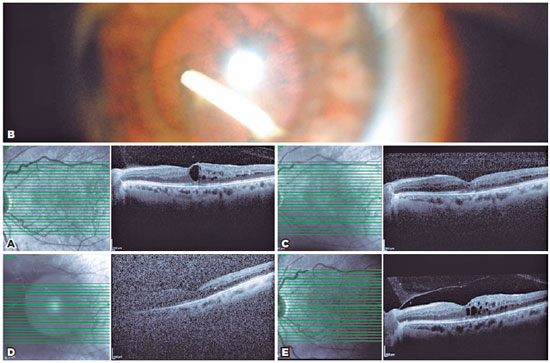

A 56-year-old woman presented with DME. Her best-corrected visual acuity (BCVA) measured 20/200, intraocular pressure (IOP) was 13 mmHg, and central macular thickness (CMT) was 400 µm in the left eye (Figure 1A). She had undergone five previous intravitreal injections of ranibizumab for her DME. Ozurdex® implant injection was performed owing to the presence of persistent DME. Following topical anesthesia with proparacaine, the implant was injected via the pars plana route 3.5 mm from the limbus. At one month after injection, slit-lamp examination revealed that the implant was located in the inferotemporal quadrant of the lens (Figure 1B) and that macular edema had resolved. Optical coherence tomography (OCT) scanning showed that the CMT had regressed from 400 to 266 µm (Figure 1C). Additionally, her BCVA measured 20/100 and IOP was 18 mmHg in the left eye. Conservative management was continued in order to determine whether the implant could be effective in the treatment of her macular edema. At three months after injection, the CMT increased from 266 to 320 µm (Figure 1D) and her BCVA decreased from 20/100 to 20/200. Surgery was planned because of cataract progression. Phacoemulsification surgery was performed at three months after injection. During phacoemulsification, Ozurdex® was divided with the crystalline lens and aspirated with a hacoemulsification probe. During phacoemulsification, posterior capsulorhexis was performed and a monofocal hydrophobic 24.00 D intraocular lens (IOL) was placed in the bag. The IOL was well centered at one week postoperatively, and the IOP was within the normal limit. At one month postoperatively, her BCVA measured 20/125, IOP was 16 mmHg, and CMT was 341 µm in the left eye (Figure 1E).

A 57-year-old woman presented with DME (Figure 3A). Her BCVA measured 20/200 and IOP was 19 mmHg in the right eye. She had received 13 previous intravitreal injections of ranibizumab for her DME. Ozurdex® implant injection was performed owing to the presence of recurrent DME. The implant was injected via the pars plana route 3.5 mm from the limbus, following topical anesthesia with proparacaine. At one month postoperatively, slit-lamp examination revealed that the implant was located in the inferotemporal quadrant of the lens (Figure 3B). Moreover, her macular edema had resolved and OCT scanning revealed that her CMT had decreased from 560 to 237 µm (Figure 3C), with the IOP being within the normal limit. Conservative management was continued to determine the effectiveness of the implant. At five months after injection, her CMT had increased from 237 to 353 µm, BCVA measured 20/400, and IOP was 20 mmHg. There was significant cataract progression; therefore, phacoemulsification surgery was performed at five months post-after injection. During phacoemulsification, posterior capsulorhexis and anterior vitrectomy were performed and a three-piece hydrophobic 21.00 D IOL (AR40E, AMO; Abbott) was placed in the sulcus. The IOL was well centered at one day postoperatively, and her IOP was within the normal limit. At one month postoperatively, her BCVA measured 20/200 and CMT was 353 µm.